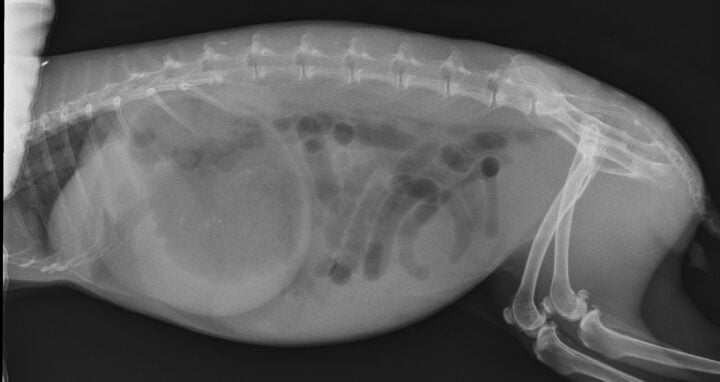

Radiography is an excellent tool to assess the presence of gastric dilation and intestinal obstruction. A retrospective study comparing radiographs of rabbits with gastrointestinal stasis and gastrointestinal obstruction identified several key features to differentiate between the two conditions (Debenham et al., 2019).

Cases of obstruction were more likely to have gastric distension where the sum of the height and length of the stomach was greater than or equal to the length from the first lumbar vertebra to the coxofemoral joint. Ninety-two percent of obstruction cases showed contact between the ventral aspect of the stomach and the ventral abdominal wall. In addition, most obstruction cases showed gastric contents consisting primarily of liquid with a “gas cap” (Figure 3A), whereas gastrointestinal stasis cases showed evidence of normal stomach ingesta (Figure 3B).

In cases of obstruction, gas in the small intestine but absent in the caecum is also a common finding (Huynh and Pignon, 2013).